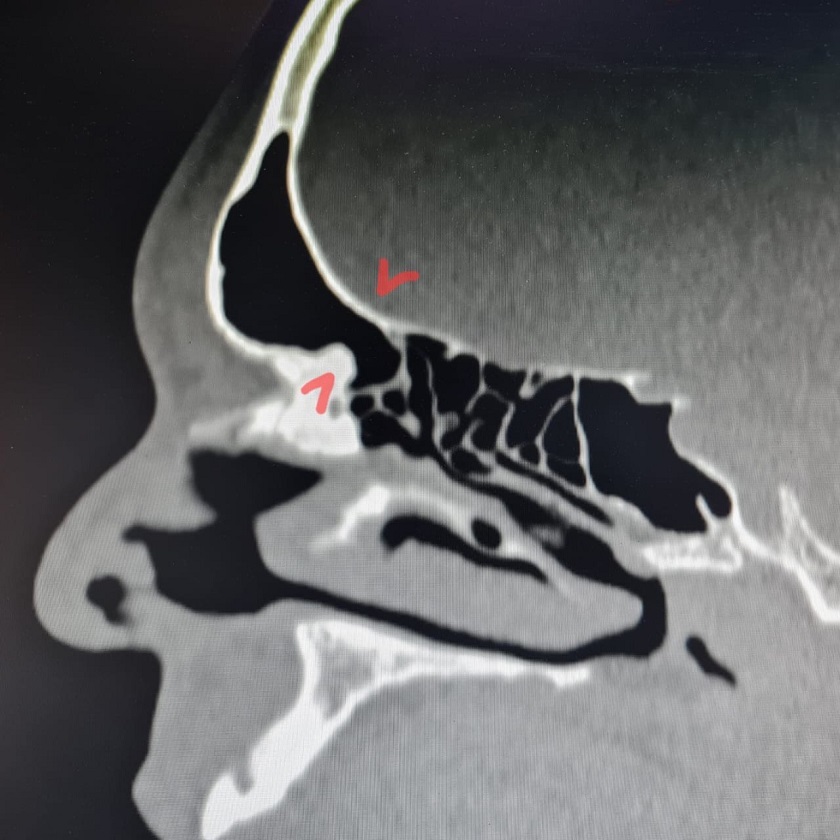

Фото: Елена Разумеева/Вконтакте. На снимке пазуха с блокированными путями оттока.

«Сложность операции заключалась в необходимости выполнения сразу нескольких вмешательств на соседних пазухах, опасности повреждения стенок пазухи и проникновения в полость черепа, малого пространства для работы инструментов и необходимости удаления большого объёма костной ткани в полости носа и пазух под контролем эндоскопа», - сообщила главврач.